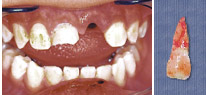

牙齒變色

1.jpg

牙齒變色分外在和內(nèi)在兩種類別。外在變色是由于食物中的色素附在牙面上,形成斑漬,只要洗牙便可以清除這類斑漬。內(nèi)在變色的其中一個(gè)原因是在乳齒或恒齒的形成過程中,受到一些藥物例如四環(huán)素的影響。另外,牙齒壞死或者蛀牙,也會(huì)引致牙齒變色。其實(shí),大部份變色的情況都可以經(jīng)過治療得到改善。如果有疑問,可以請(qǐng)教您的牙科醫(yī)生;要是學(xué)童已經(jīng)參加牙科保健,我們的牙科醫(yī)生和牙科治療師會(huì)給您適當(dāng)?shù)慕ㄗh。